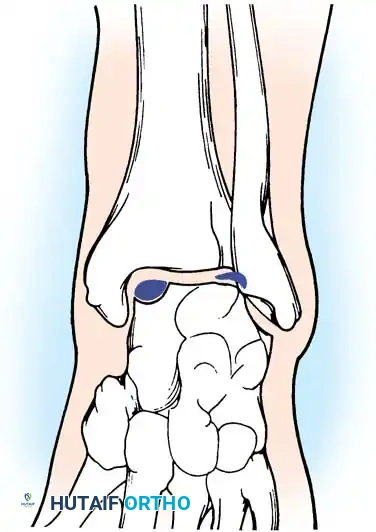

Osteochondral Lesions of the Talus (OCD)

Osteochondral lesions of the talus (OLT), historically termed osteochondritis dissecans by König in 1888 and later applied to the ankle by Kappis in 1922, represent a localized injury to the articular cartilage and underlying subchondral bone.

While the Berndt and Harty radiographic classification (Stages I-IV) is historically significant, MRI is the current gold standard for evaluating the size, depth, and stability of the cartilage cap, as well as the presence of subchondral cysts.